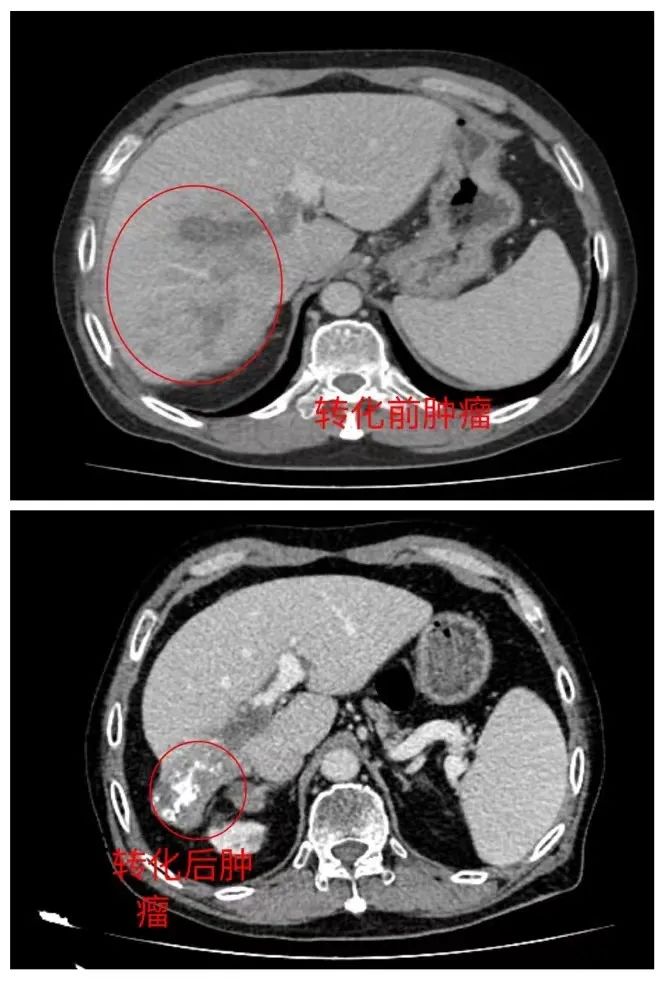

入院后,通过对患者病情资料的详细分析查阅,潘耀振教授说:“林大叔的难题主要在于肿瘤巨大并有大血管癌栓同时肿瘤还侵犯了右侧肾上腺,手术无法Ⅰ期根治性切除。”基于这种情况,潘耀振教授团队在充分评估病情及联合肝癌MDT团队研讨治疗方案后,决定为林大叔先行肝癌的转化治疗,即先通过介入+免疫+靶向治疗,将肿瘤缩小,同时使正常肝组织增大,待到时机成熟,再予以根治性手术切除肿瘤。

得知自己还“有救”,林大叔和家里商量后同意了该治疗方案。于是,林大叔积极配合完成了6个周期的转化治疗及4次介入手术治疗,其状态也越来越好,疼痛也减轻很多,复查肿瘤明显缩小,肿瘤指标也持续下降,初步转化获得成功!再次复查,肝功能评估为Child-PughA级,具备手术切除可行性,以上均提示具有手术指征,王兴副主任组织了肿瘤多学科会诊,经过充分评估,患者身体情况良好,可以耐受手术,是施以根治性手术的绝佳时机。

一切术前准备就绪后,林大叔进行了肿瘤切除手术,在手术室及麻醉科的保驾护航下,潘耀振教授主刀,带领王兴副主任及团队成功完成了手术。术后在肝胆外科护理团队运用快速康复管理及精心护理下,林大叔的身体各项指标迅速恢复,没有任何并发症发生,术后病理提示切除的肝组织见大片坏死,无肿瘤组织残留,肝切缘无病变组织。术后复查肝癌肿瘤标记物等指标均正常。